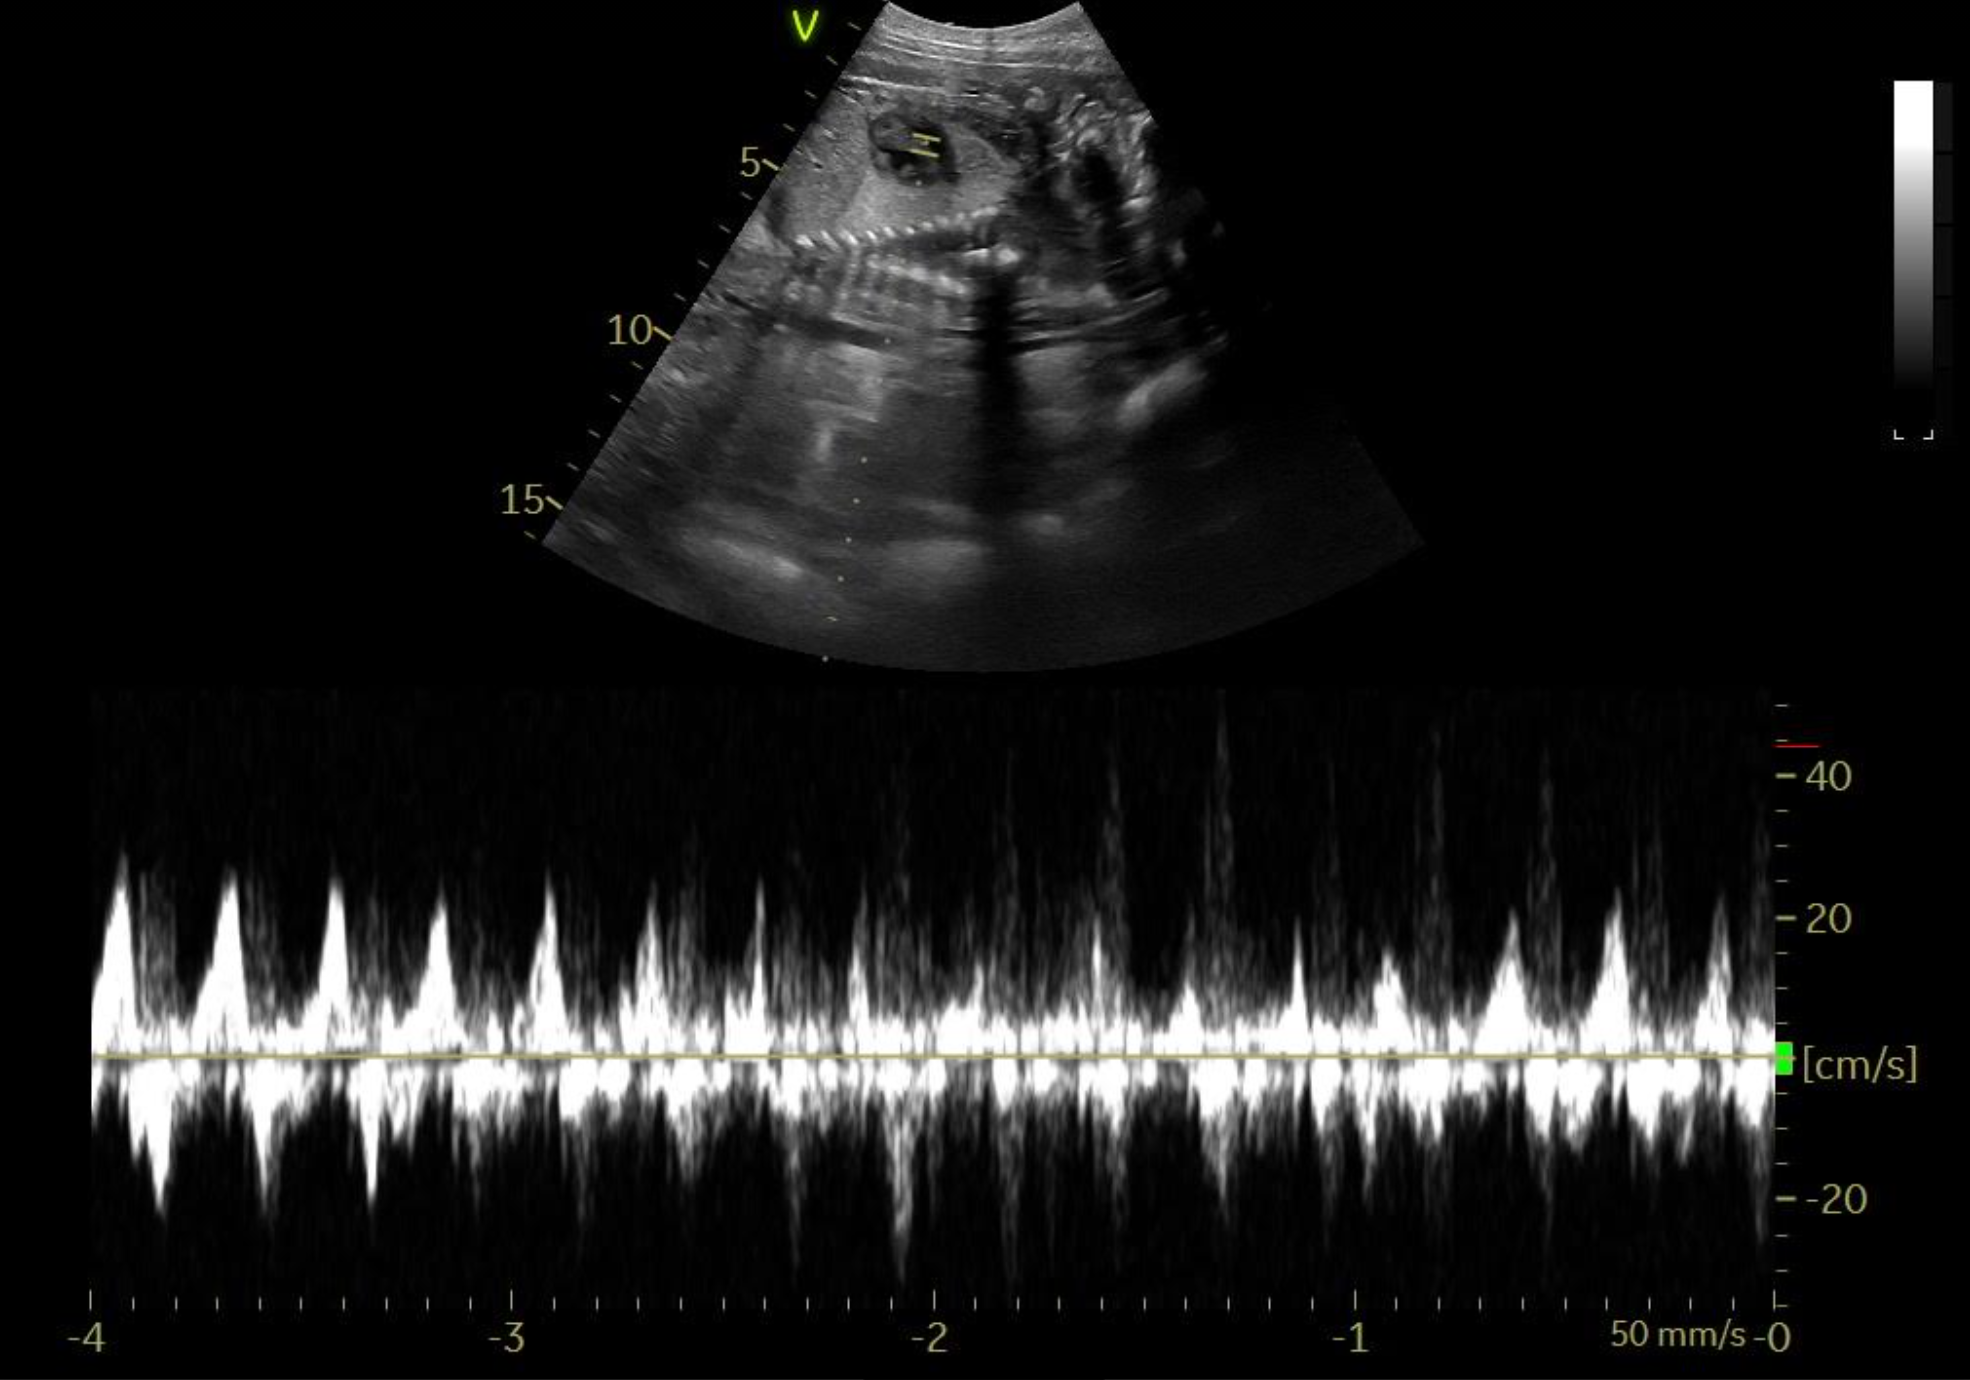

Tessa er scannet igen. Hvalpene er alle i live og har det godt. Deres hoveder er målt til 2 cm.

23.03.2021

Tessa er scannet drægtig. Hvalpene er sunde og er målt til 1,5 cm.